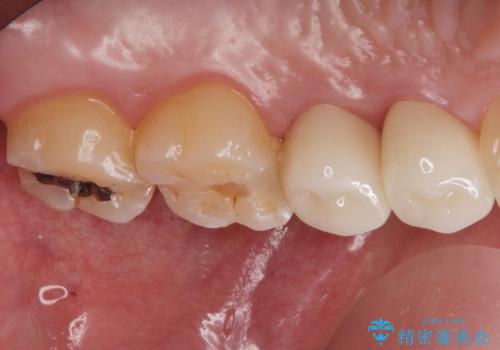

拡大鏡下で銀の詰め物、古いプラスチックの樹脂を外し、虫歯が残ってないかを確認して

ジルコニアクラウンで治療を行いました。

白い被せ物を入れたことにより銀が目立たなくなり

染みることもなくなりました。

ご希望に沿った治療となり大変満足して頂けました。